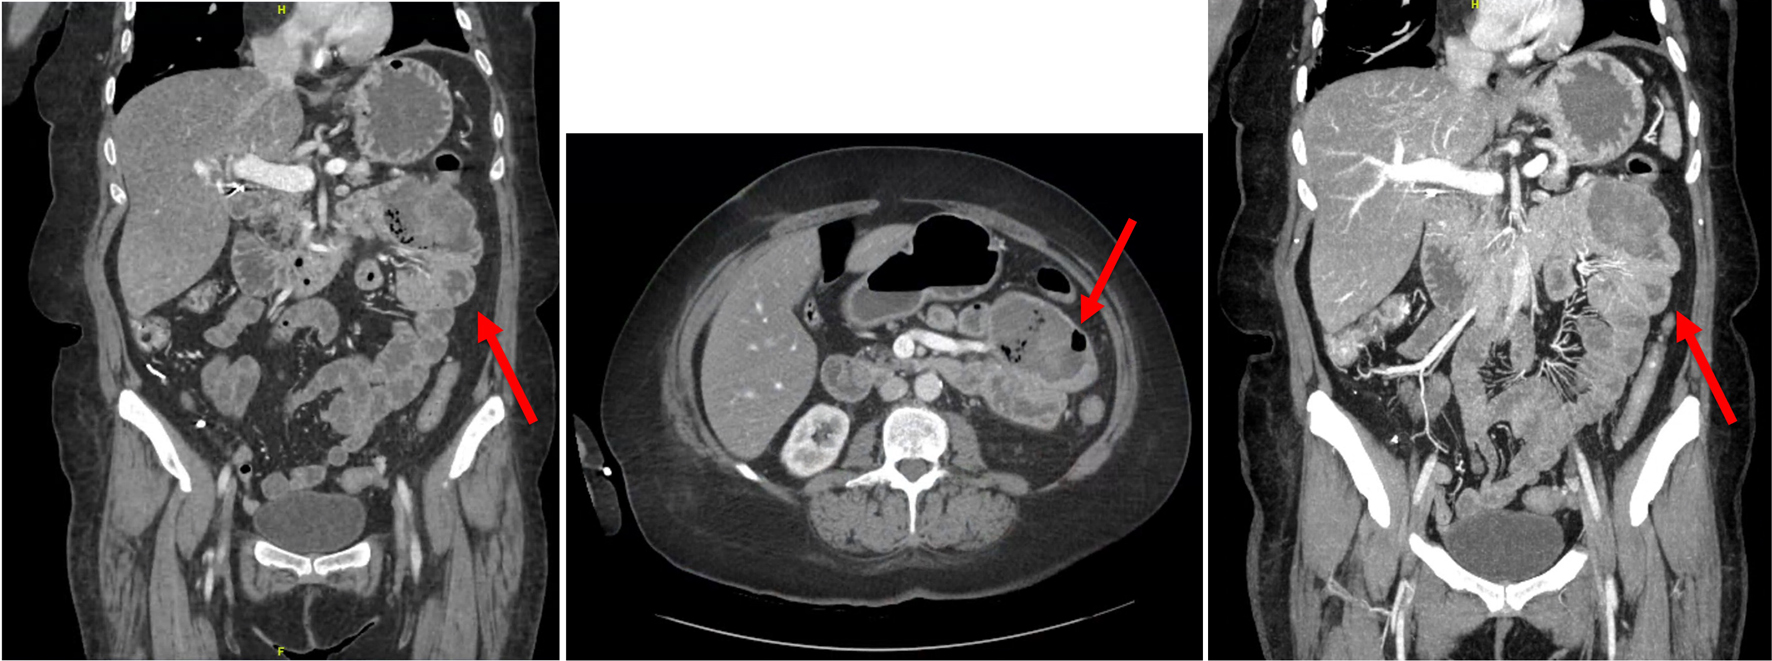

Due to the unclear source of GI bleeding, the patient underwent CT enterography, which demonstrated abnormally dilated conglomerate loops of the small bowel in the proximal bowel, which was suspicious for possible metastatic diseases (Fig. 2). This area was consistent with FDG avid lesions. She then underwent a push enteroscopy that showed two large, discrete, friable, and ulcerated masses in the distal duodenum and proximal jejunum. The mass in the duodenum was found in the fourth portion of the duodenum and was fungating with evidence of recent bleeding. The jejunal mass was polypoid in nature with no evidence of bleeding (Fig. 3). Since she had been symptomatic from her anemia due to GI bleeding which required blood transfusion each week, as well as her Eastern Cooperative Oncology Group (ECOG) performance status being zero at this time, she was recommended to have small bowel resection to improve her quality of life. The patient was aware that this procedure was intended to be curative.

![]() Click for large image | Figure 2. Images from CT enterography in coronal and axial views revealing an abnormally distended conglomerate of small bowel loops (indicated by the red arrows) within the left upper abdominal quadrant measuring 7.3 × 4.9 cm, suggestive of a proximal jejunal mass. CT: computed tomography. |